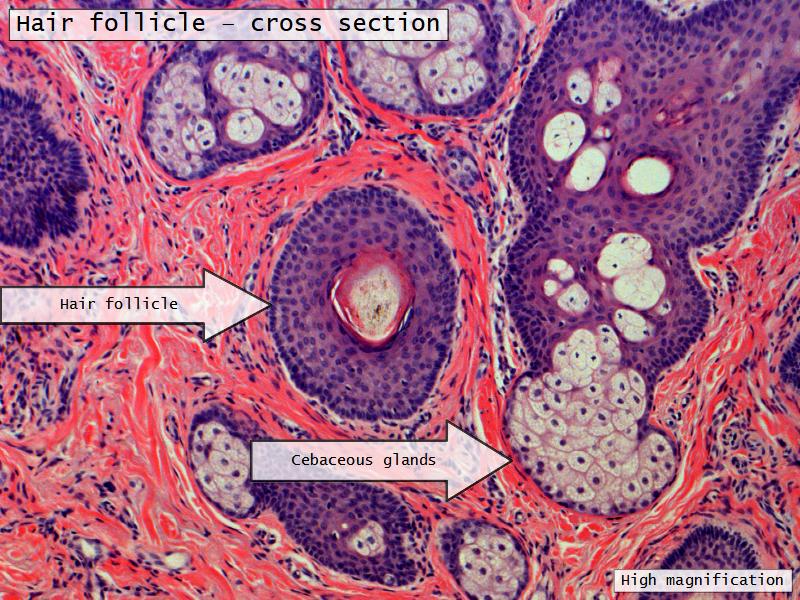

Slides: Respiratory System

- Slide 71: Nostril

Nostril